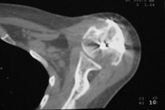

В момент осмотра: нормостеническая конституция, по передней поверхности плечевого сустава – рубец. Рука в положении приведения. Отведение не более 10 град, дальнейшие движения с лопаткой до 20-25 град. Амплитуда сгибания-разгибания 10-15 град. Ротация отсутствует. Пальпаторно - выраженная болезненность над суставом, особенно в проекции клювовидного отростка. При попытках пассивных движений – боль. Рентгенограммы и результаты КТ приложены(b2(3)_xr.jpg, b1(6)_ct.jpg).

Диагноз: неправильно сросшийся в условиях накостного остеосинтеза оскольчатый перелом головки левой плечевой кости (11-С3.2), асептический некроз головки плечевой кости, смешанная артро-миогенная контрактура левого плечевого сустава; демиелинизирующая нейропатия левого локтевого нерва.

Анализ ситуации позволяет считать, что основными причинами контрактуры являются неправильная репозиция фрагментов головки (разворот кверху и кзади), асептический некроз головки плечевой кости (отчетливое склерозирование на СТ).